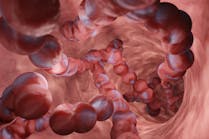

Sepsis pathophysiology

The pathophysiology of sepsis is complex. Recent theories describe a host’s global response to infection as having both pro-inflammatory and compensatory anti-inflammatory stages.9 The exact sequence of events is unclear. One theory supports a sequential model in which inflammation is followed by anti-inflammation, while a second model, known as the mixed antagonist response syndrome, suggests that these two occur simultaneously. Dysregulation of the inflammatory/anti-inflammatory response may contribute to sepsis-related mortality. A prolonged hyper-inflammatory response results in a storm of toxic cytokines, while an immunosuppressive stage impairs protection against pathogens. No matter the sequence, dysregulation of the immune response to an infection leads to altered coagulation and cellular activation, endothelial cell failure, and cellular apoptosis, all of which contribute to metabolic alterations and multi-organ damage, and eventually death.10 A clear understanding of sepsis pathophysiology is crucial for development of novel therapeutic and diagnostic tools.